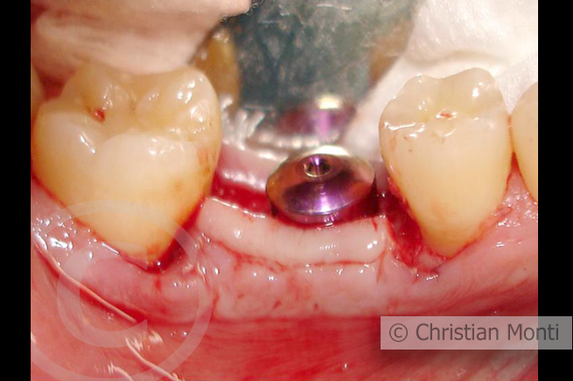

EDENTULIA SINGOLA

Impianto dilazionato in sostituzione di un molare inferiore